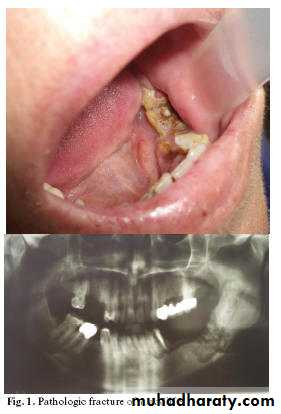

Oral manifestations

Include: tumors of the maxilla or mandible that cause :• bone destruction

• mobility of the teeth,

• pain and paresthesia.

• On radiograph it. appears as an osteolytic lesion with poorly demarcated margins.